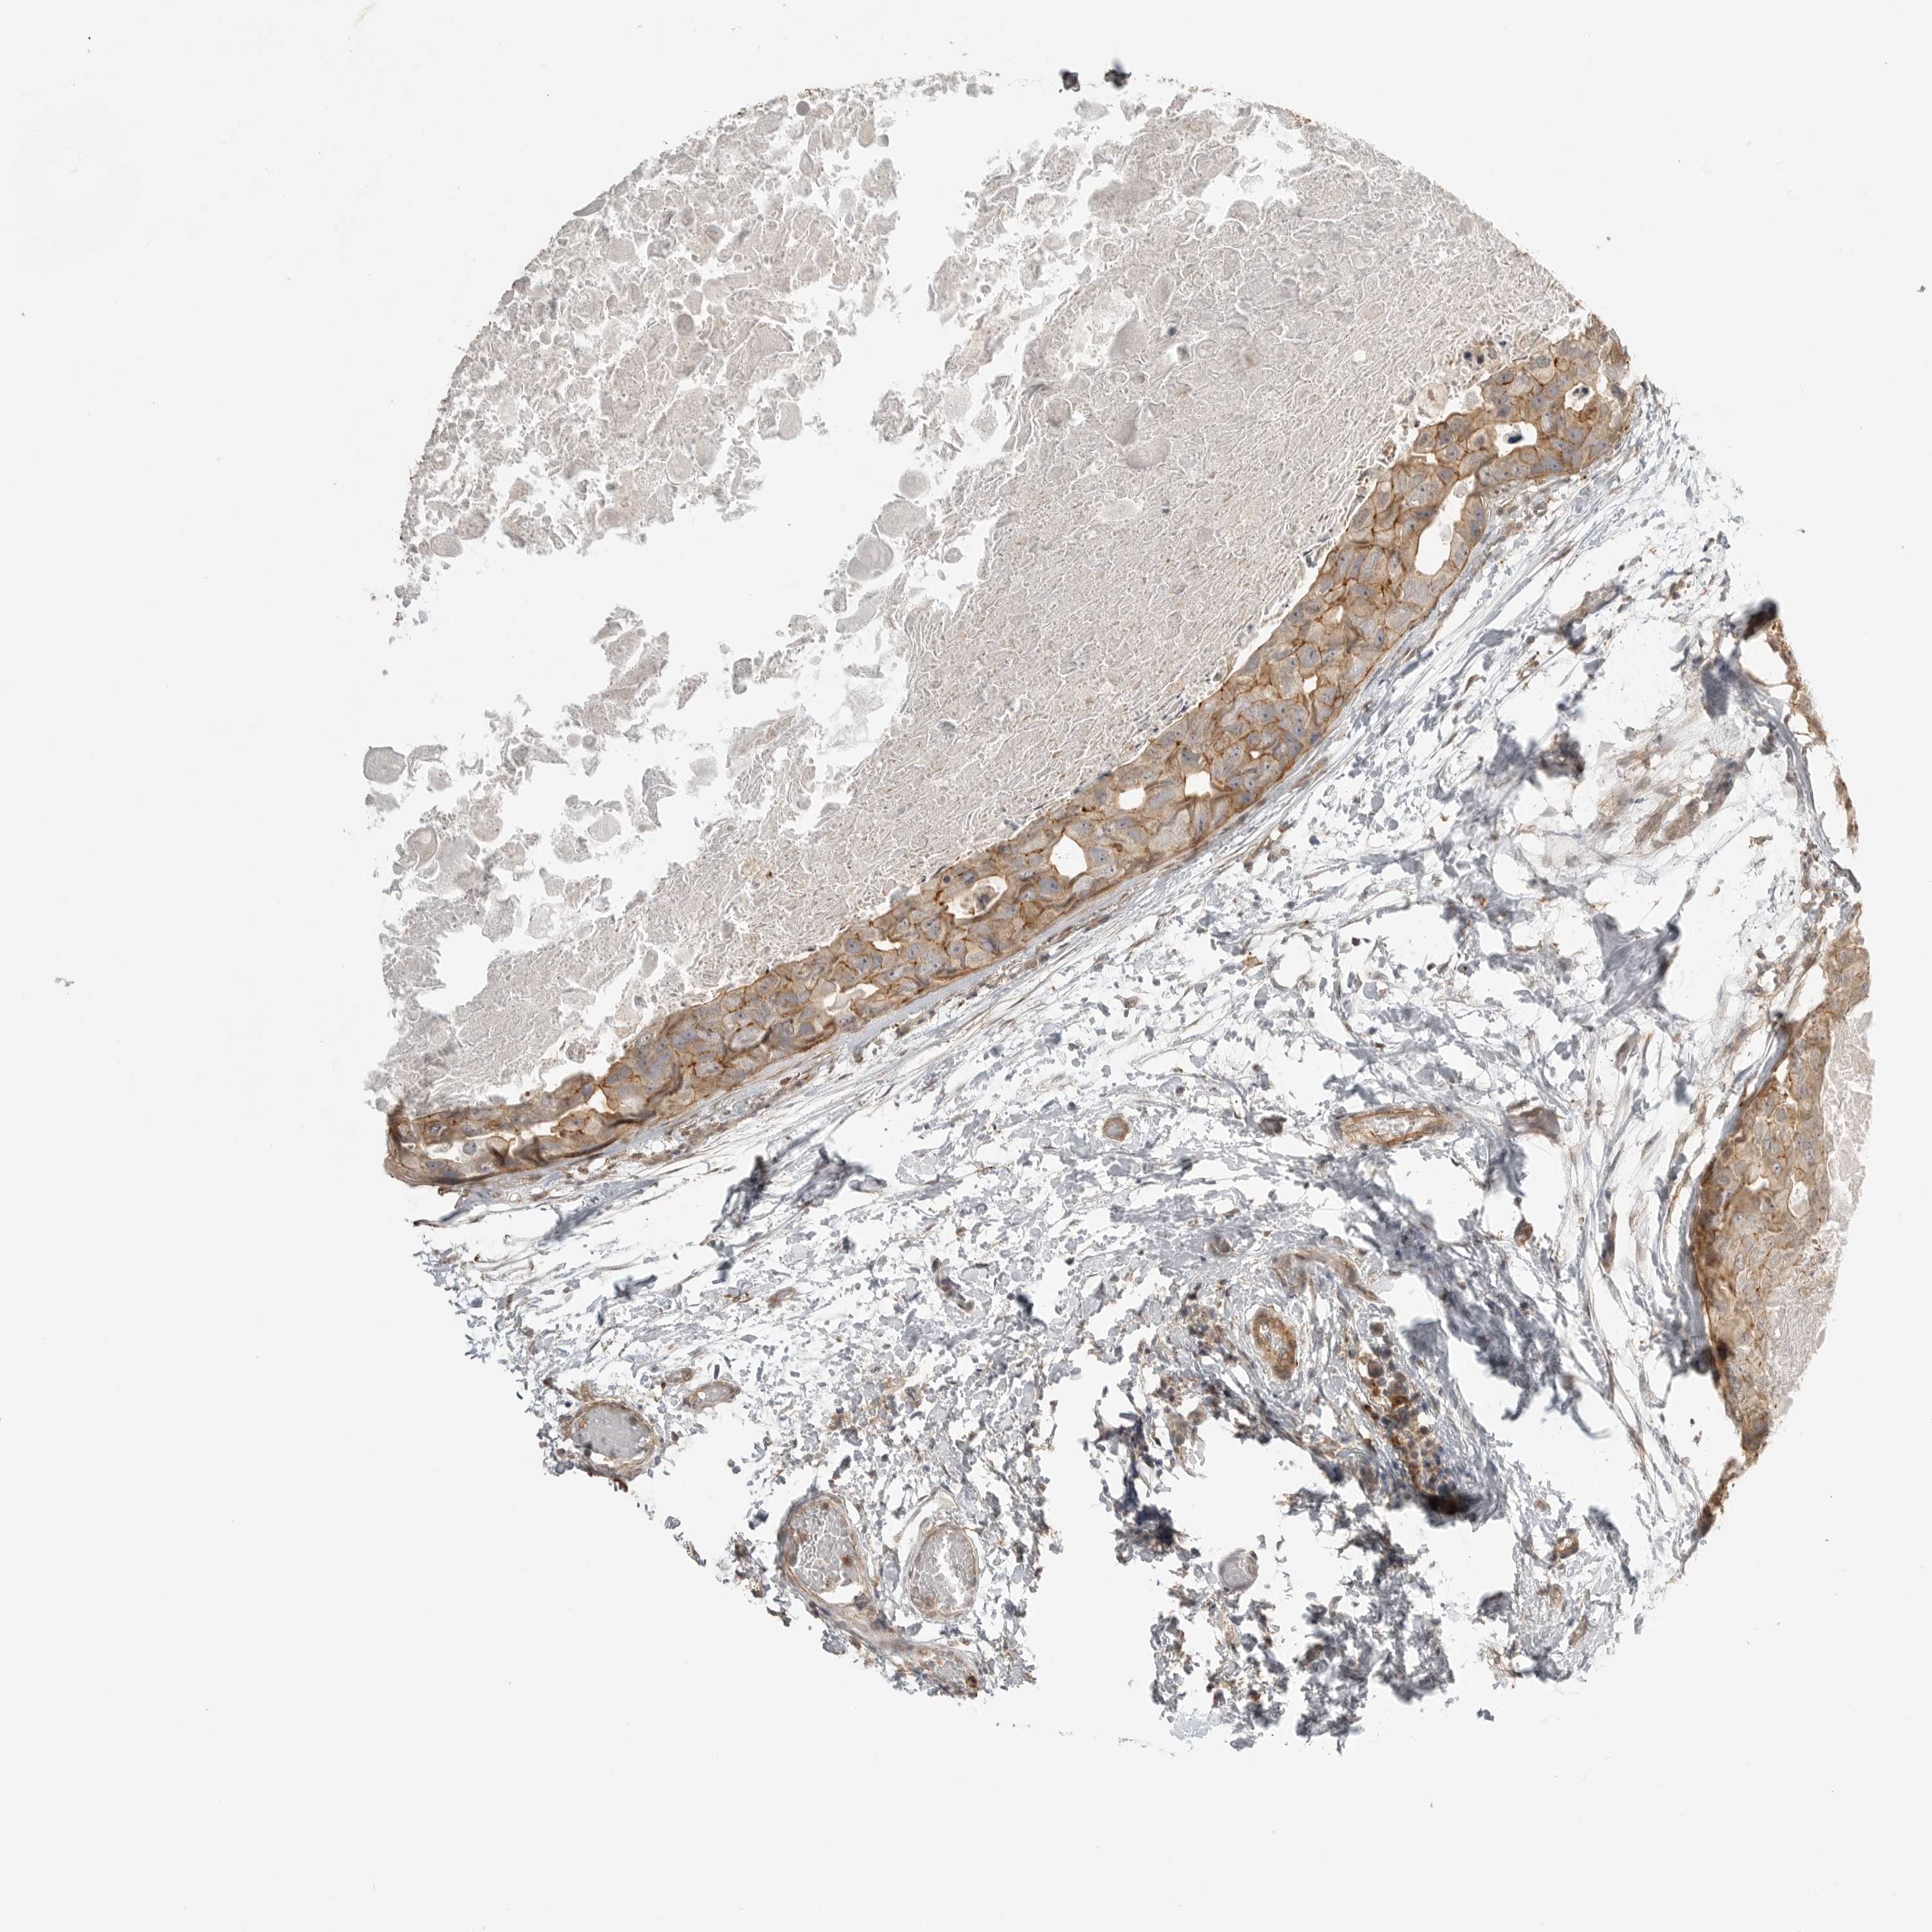

GPC2

CANCER BREAST CANCER Show tissue menu

BRCA TCGA BRCA VALIDATION PROTEIN EXPRESSION

Breast cancer

Human cancer